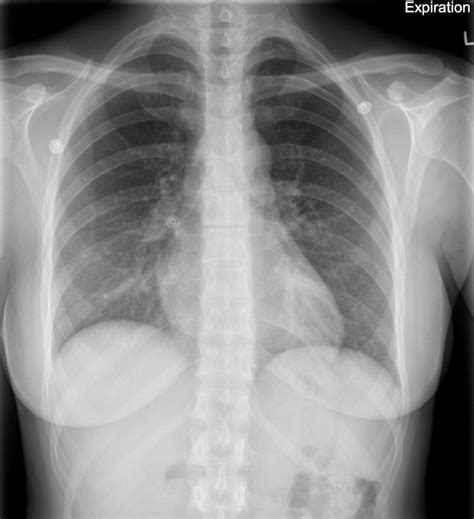

Chest XRay in Pneumothorax

Chest XRay in Pneumothorax from fpnotebook.com

The diagnosis of pneumothorax using ultrasound is accurate and reliable; Supine pneumothorax) for the identification of pneumothorax after blunt trauma. Since then there have been many studies that have shown bedside ultrasound can rapidly detect pneumothorax, helping avoid serious potential consequences (i.e. These are the thoracic radiographs: 3 article feature images from this case Home ultrasound library a pneumothorax is an abnormal collection of gas in the pleural space, separating the parietal pleura of the chest wall from the visceral pleura of the lung. Ultrasound appearance of pneumothorax explained. Pneumothorax can be missed by bedside radiography, and computed tomography is the current alternative.

Nov 08, 2017 · primary spontaneous pneumothorax: Ultrasound outperforms cxr in evaluation of pneumothorax in blunt trauma patients, but there cite this article as: Lack of ionizing radiation and easy operation are benefits of this imaging technique. 1 traumatic pneumothorax is common in dogs, whereas spontaneous pneumothorax is relatively rare. In the supine trauma patient, this will typically be the anterior chest wall lateral to the sternum in the second intercostal space. When m mode is used on a normal lung, the lung (and the air inside it) moves back and forth across this single ultrasound beam creating a picture that is often compared to a sandy beach. To evaluate for pneumothorax with ultrasound, have the patient lay supine. A pneumothorax separates the visceral and parietal pleura, eliminating normal lung sliding between these layers on lung us. Among 302 analyzable controls, 65 had absent lung sliding, 16 of them showed an a line sign, and none showed a lung point. Since then there have been many studies that have shown bedside ultrasound can rapidly detect pneumothorax, helping avoid serious potential consequences (i.e. These are the thoracic radiographs: Thoracic ultrasound has more sensitivity than a supine chest radiograph (see: Identification of a lung point on lung us yields 100% specificity for pneumothorax (58).